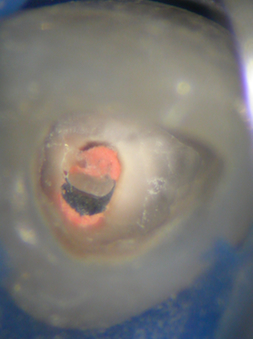

Veröffentlicht 1. Dezember 2008 am 253 × 339 in Thermafil-Revision (1)

Kanaleingang mit carrierbasierter WF